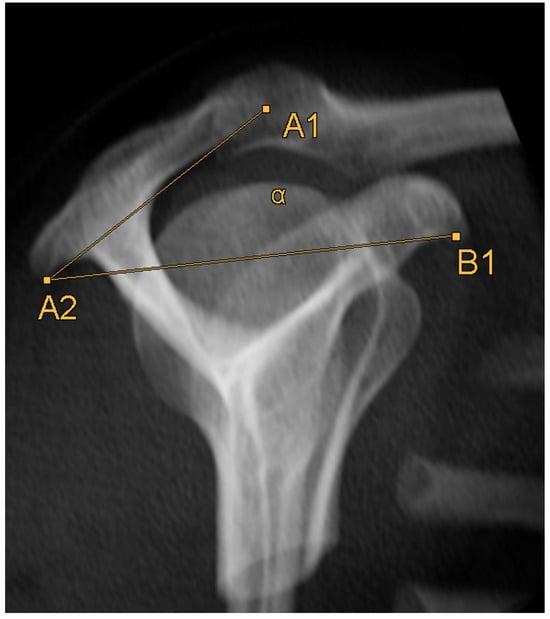

2.3. Acromion Index (Figure 1)